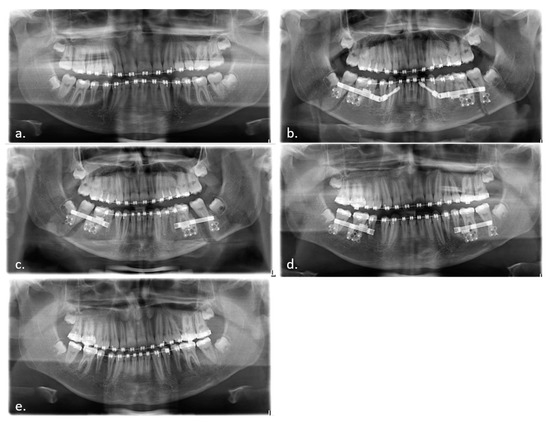

Figure 4.

Lateral skull view (a) before and (b) after treatment with IMDO.